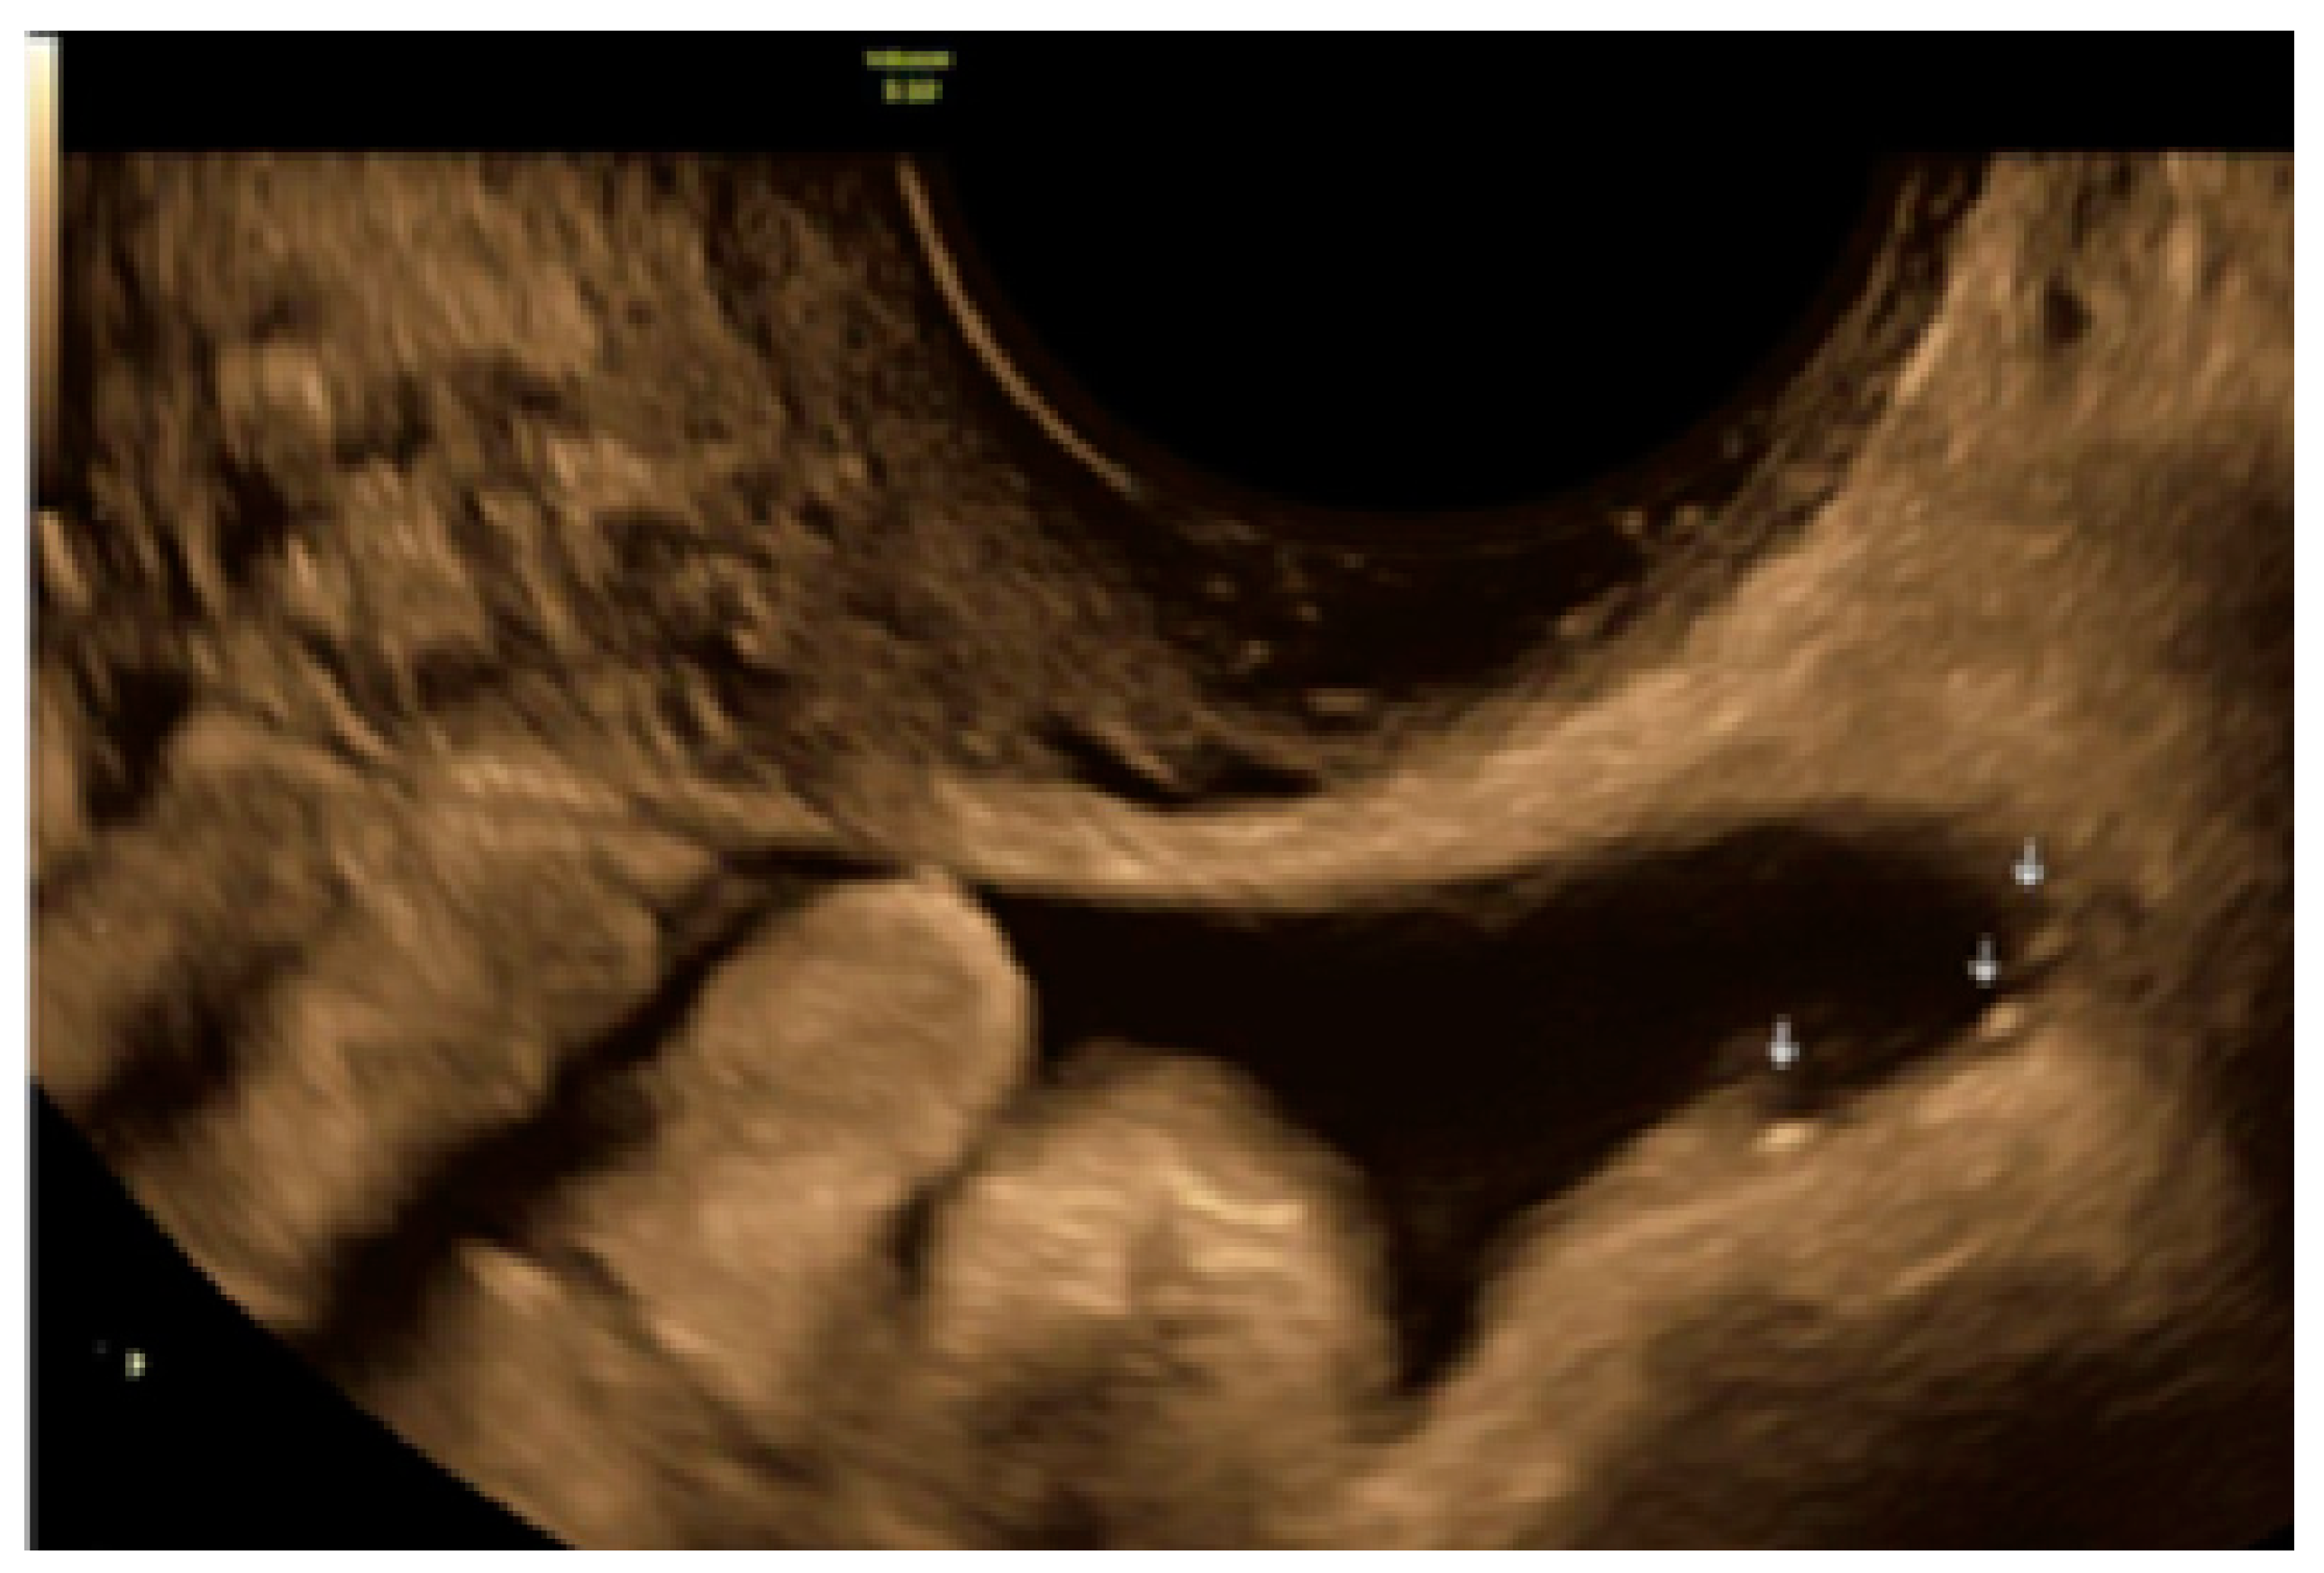

3.2. Cystic Multiple Separate Lesions

3.3. Cystic Lesions Arranged in a Cluster